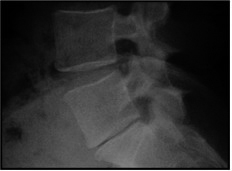

Die weitaus meisten Rückenprobleme sind duch einen relativ früh beginnenden Verschleissprozess der Wirbelsäule bedingt.